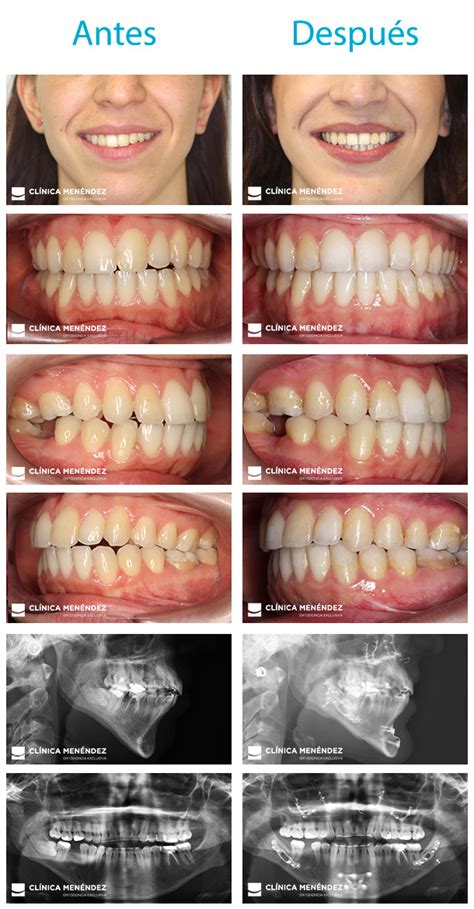

Paola Olmedo antes y después de la cirugía ortognática. Fuente: telecinco.es